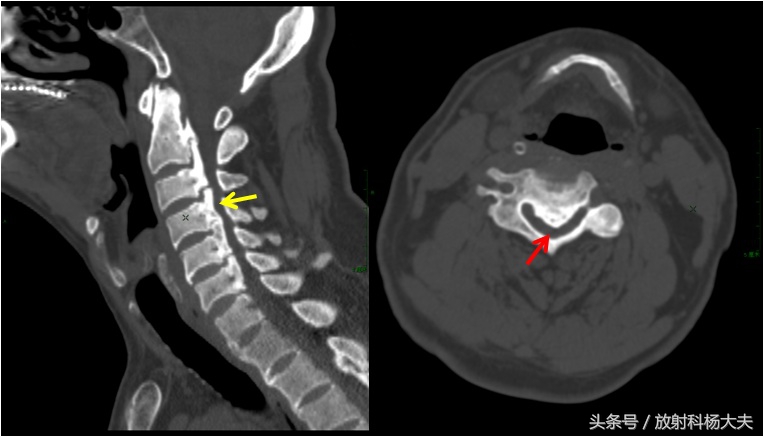

CT图,左图黄箭为后纵韧带骨化,右图红箭为椎管,严重狭窄

有时候轻度的OPLL在普通X线片上不容易被发现,此时CT具有很好的确诊价值,对病变范围,程度显示的更佳清晰,利于术前指导。